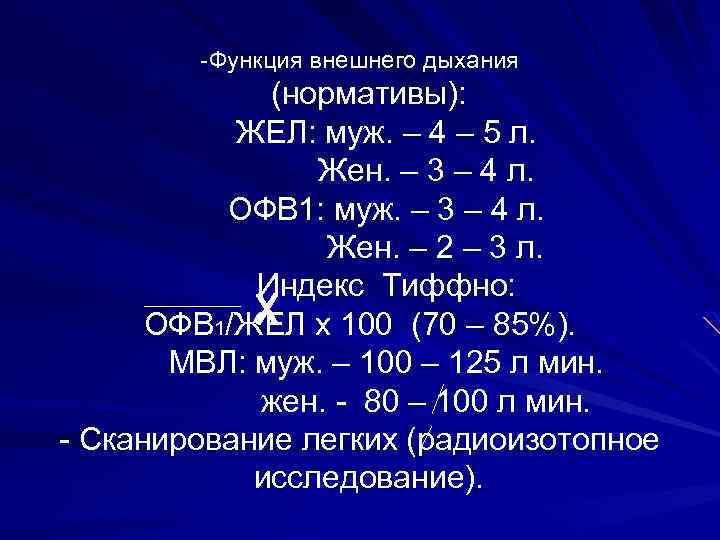

-Функция внешнего дыхания (нормативы): ЖЕЛ: муж. – 4 – 5 л. Жен. – 3 – 4 л. ОФВ 1: муж. – 3 – 4 л. Жен. – 2 – 3 л. Индекс Тиффно: ОФВ 1/ЖЕЛ х 100 (70 – 85%). МВЛ: муж. – 100 – 125 л мин. жен. - 80 – 100 л мин. - Сканирование легких (радиоизотопное исследование).